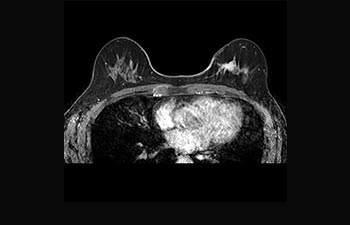

Sehen Sie selbst, was die ersten Nutzer von Ingenia Prodiva 1.5T über ihre Erfahrungen mit dem System und dessen Auswirkung auf ihre radiologische Praxis berichten.